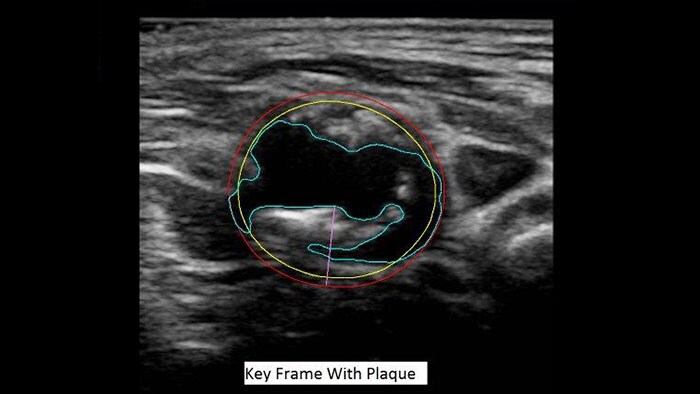

A novel measurement of atherosclerotic plaque volume

US Q-App Vascular Plaque Quantification (VPQ) helps you perform comprehensive volume analysis for carotid plaque; a significant indictor in cardiovascular disease. Automatically measure plaque composition throughout a captured volume, percent area vessel reduction and other characteristics using 3D technology. Results may be posted to patient exams.

Benefits